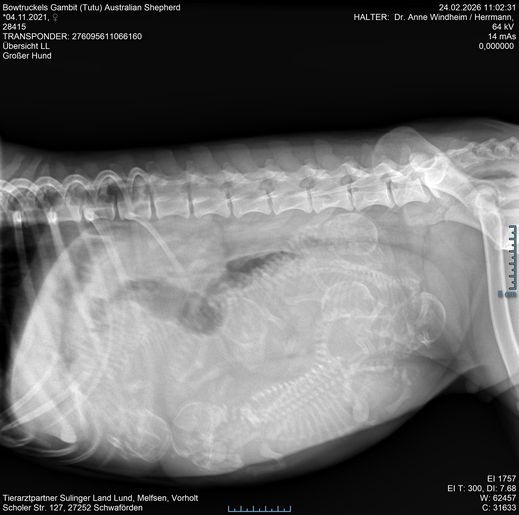

Heute haben die Auswertung von Hetties HD-Röntgen bekommen. Die Ergebnisse sind nahezu perfekt:

HD A2    ED 0    OCD bds.frei  LÜW 1

Wir freuen uns sehr, damit stünde einer möglichen zukünftigen Zuchtverwendung von Hettie nichts im Wege.